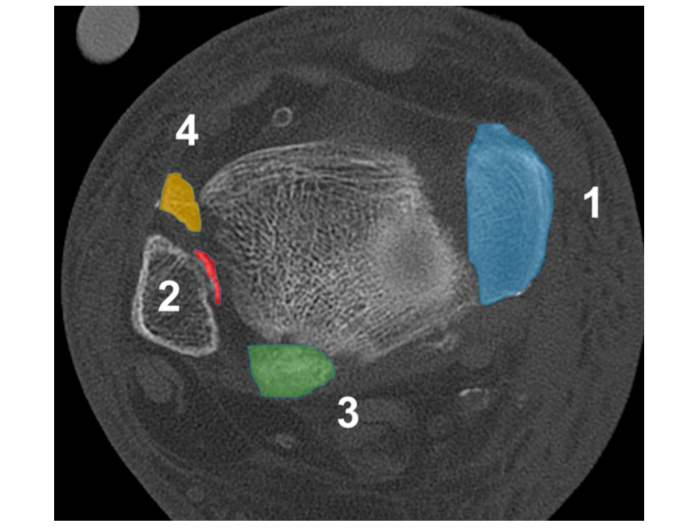

① 四踝骨折示意图:1.内踝;2.外踝;3.后踝;4.胫骨前结节(前踝)。

② 四踝骨折典型病例图。